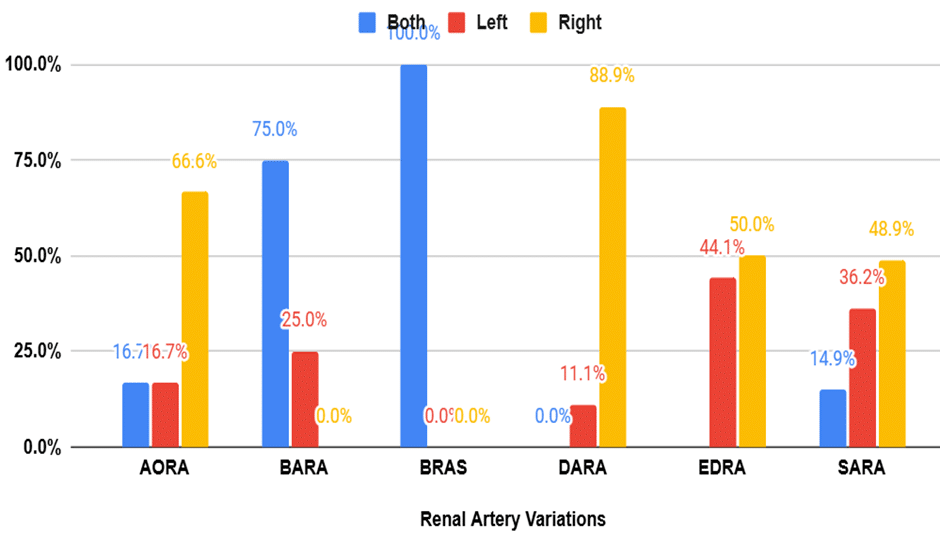

Evaluation of Renal Artery Variations Among Patients Undergoing Abdominal Computed Tomography in an African Population

Background: Renal artery variations (RAV) are common anatomical deviations that can significantly impact clinical outcomes in surgical and interventional procedures....Read More